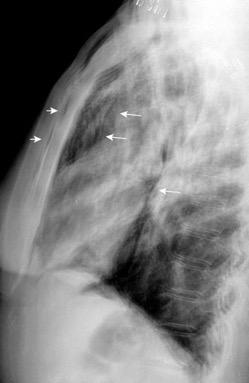

Consolidación por Infarto pulmonar. (TEP)

Visible en 2/3 posteriores

El corazón borra el1/3 anterior

Hemidiafragma izquierdo Atelectasia de la pirámide basal izquierda borrando la parte medial y posterior.